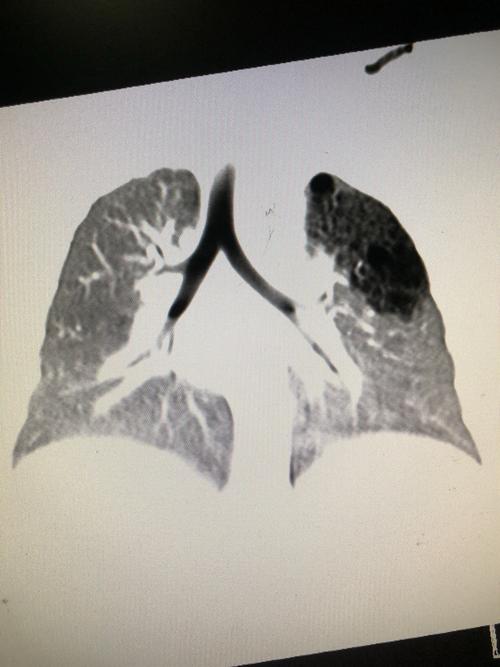

肺囊腺瘤:今天遇到一个罕见病例给大家分享一下!

先天性肺囊腺瘤